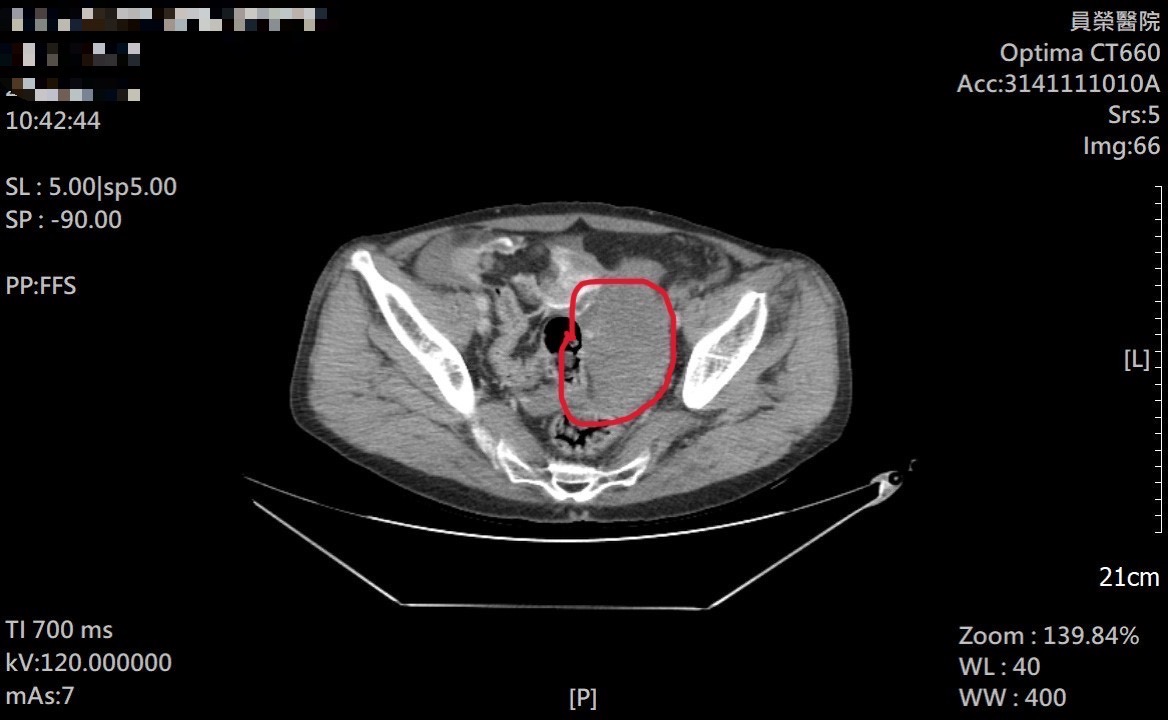

急診團隊立即施予止痛藥物,並安排抽血、X光及電腦斷層檢查。雖然四肢與頭部影像未見明顯骨折,但CTA影像顯示疑似腸系膜出血。考量患者年齡及既往心血管病史,包括心臟支架、肺部手術及長期吸菸史等高風險因素,醫師迅速啟動緊急轉診。